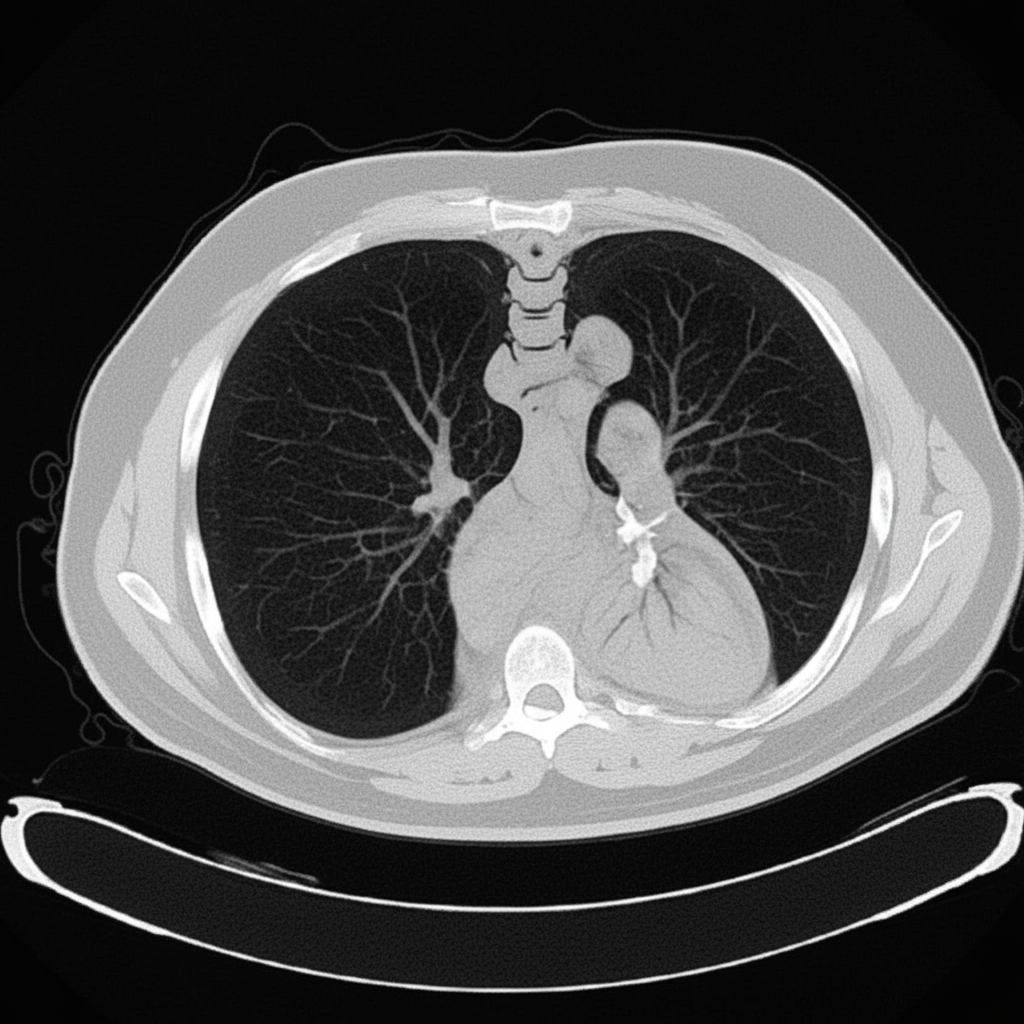

Explanation: ***CT chest without contrast*** - The image displays detailed **cross-sectional anatomy** of the chest, including the lungs, mediastinum, and cardiac structures, without any evident enhancement of blood vessels or organs. - The varying **grayscale densities** accurately depict different tissue types (e.g., air in lungs as black, bone as white, soft tissues as shades of gray) as expected in an **unenhanced CT scan**. - The **cross-sectional detail** and high resolution are characteristic of a **CT scan**. *Barium swallow study* - The image provided is a **CT scan of the chest**, not a barium swallow study. A barium swallow study involves administering barium contrast and taking X-rays to visualize the esophagus. - The density and grayscale variations seen in the image are characteristic of a CT, which uses X-rays to create cross-sectional images of body structures, and not of the high-contrast white appearance of barium within an organ lumen. *CT chest with contrast* - This image does not demonstrate enhancements of vascular structures or organs typically associated with the administration of **intravenous contrast material**. - Without the presence of **hyperdense (bright) opacification of blood vessels** (like the aorta or pulmonary arteries) or soft tissues, it is less likely to be a contrast-enhanced study. *X-ray chest* - While an X-ray chest is used to visualize chest structures, this image exhibits **cross-sectional detail** and high resolution that is characteristic of a **CT scan**, rather than a plain film X-ray. - An X-ray chest provides a 2D projection, whereas this image clearly shows a 3D cut through the chest organs with distinct tissue densities.